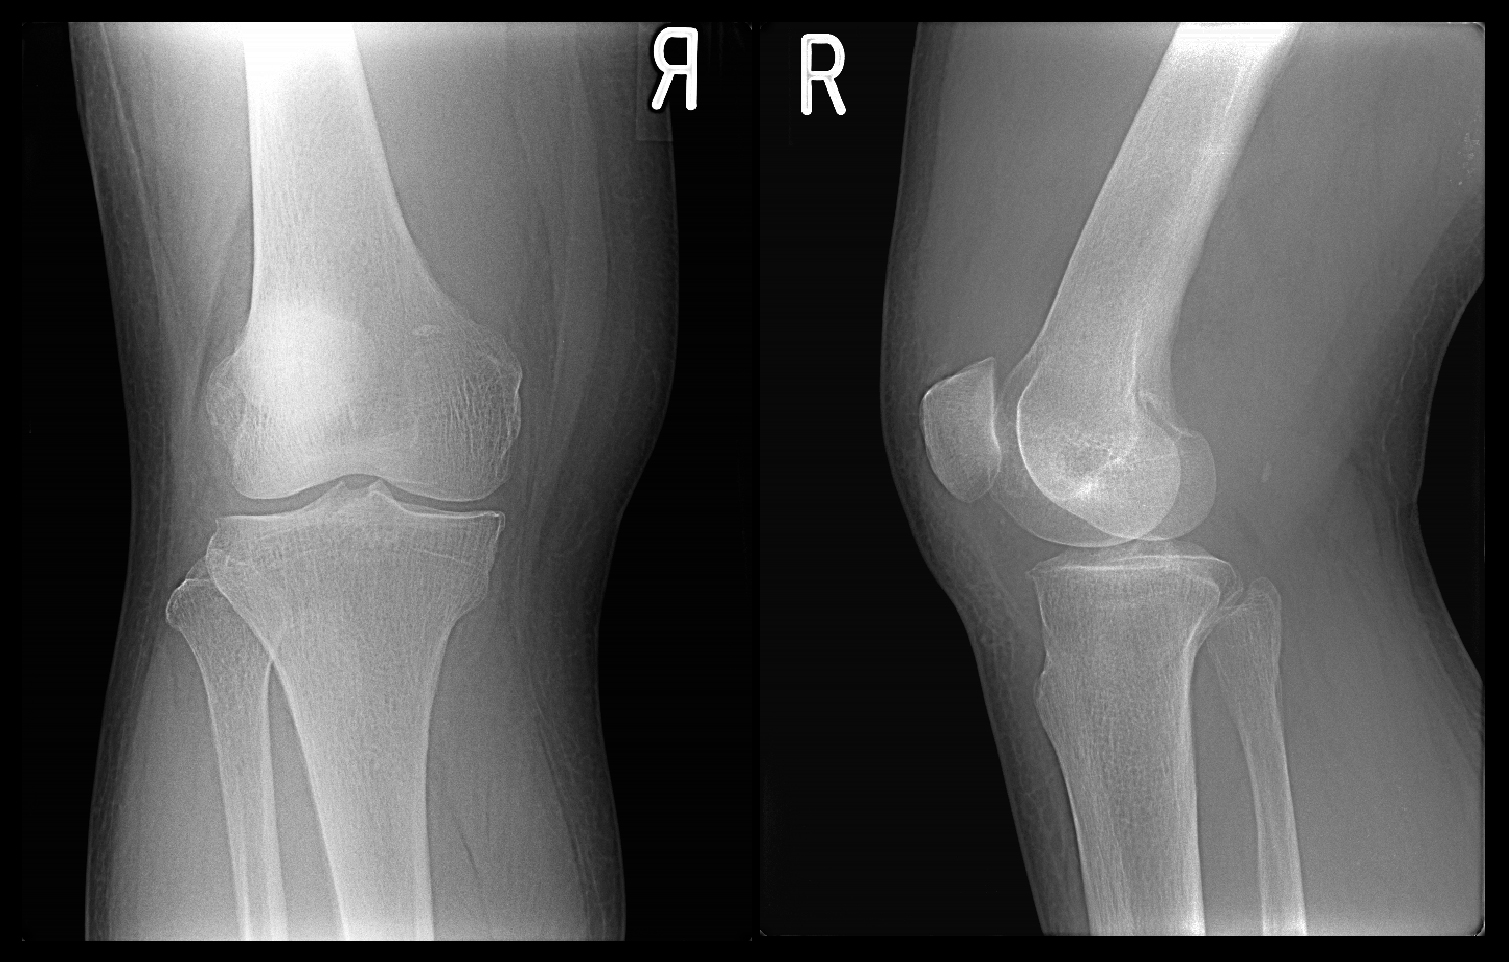

68才の女性で、椅座からの立ち上がりで右膝の後ろ側(膝窩部と言います)に重度の痛みが発症し、ほぼ歩行不能の状態で平成29年10月10日に受診されました。膝痛で重度の歩行困難は、膝に水が溜まること(膝関節水症)で起こりやすいのですが、そのような状態は膝の触診で直ぐに判断できます。この患者さんは膝関節水症の所見はありませんでした。

68才女 Xp1.jpg

それ以外にも変形性膝関節症にみられる理学所見(視診や触診でえられる所見です)は確認されず、またレントゲン像も正常で、当初私は腰椎に起因する膝痛ではないかと推察しました。